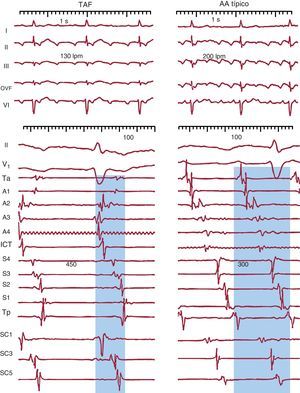

Diagnóstico electrocardiográficoTaquicardia auricular focalLa taquicardia auricular focal (TAF) se define como un ritmo auricular rápido, regular, no originado en el nódulo sinusal, con ondas P de morfología estable en el ECG y que precisa sólo de estructuras auriculares para su mantenimiento1 (Figura 1). La alternancia de ondas P y líneas de base estables indica que la taquicardia así definida en el ECG sea de mecanismo focal (TAF) con periodos de reposo entre descargas del foco (Figura 2), pero hay excepciones a esta regla.

Figura 1. Electrocardiograma y registros endocárdicos de taquicardia auricular focal y aleteo auricular típico en un mismo paciente. Los paneles inferiores muestran registros endocárdicos bipolares de la aurícula derecha anterior (Ta-A4 de arriba abajo), el istmo cavotricuspídeo, la aurícula derecha septal de abajo arriba (S4-Tp) y el seno coronario de proximal a distal (SC1-SC5). El sombreado azul muestra la porción del ciclo de la taquicardia cubierta por la activación, < 50% en la taquicardia auricular focal y el 100% en el aleteo auricular, incluso considerando sólo registros de aurícula derecha. AA: aleteo auricular; ICT: istmo cavotricuspídeo; OVF: onda de velocidad de flujo; SC: seno coronario; TAF: taquicardia auricular focal.

Aleteo auricularSe ha denominado clásicamente aleteo auricular (AA) o flutter a una taquicardia auricular de muy alta frecuencia (240-350 lpm), con ondas auriculares que producen una oscilación continua sin línea de base plana1 (Figura 1). Este patrón indicaría actividad continua durante todo el ciclo de activación auricular, como en el caso del AA típico (común) (Figura 3), pero puede haber un patrón de ondulación continua en TAF rápidas, en las que la duración de la onda P es muy próxima a la longitud de ciclo (LC).